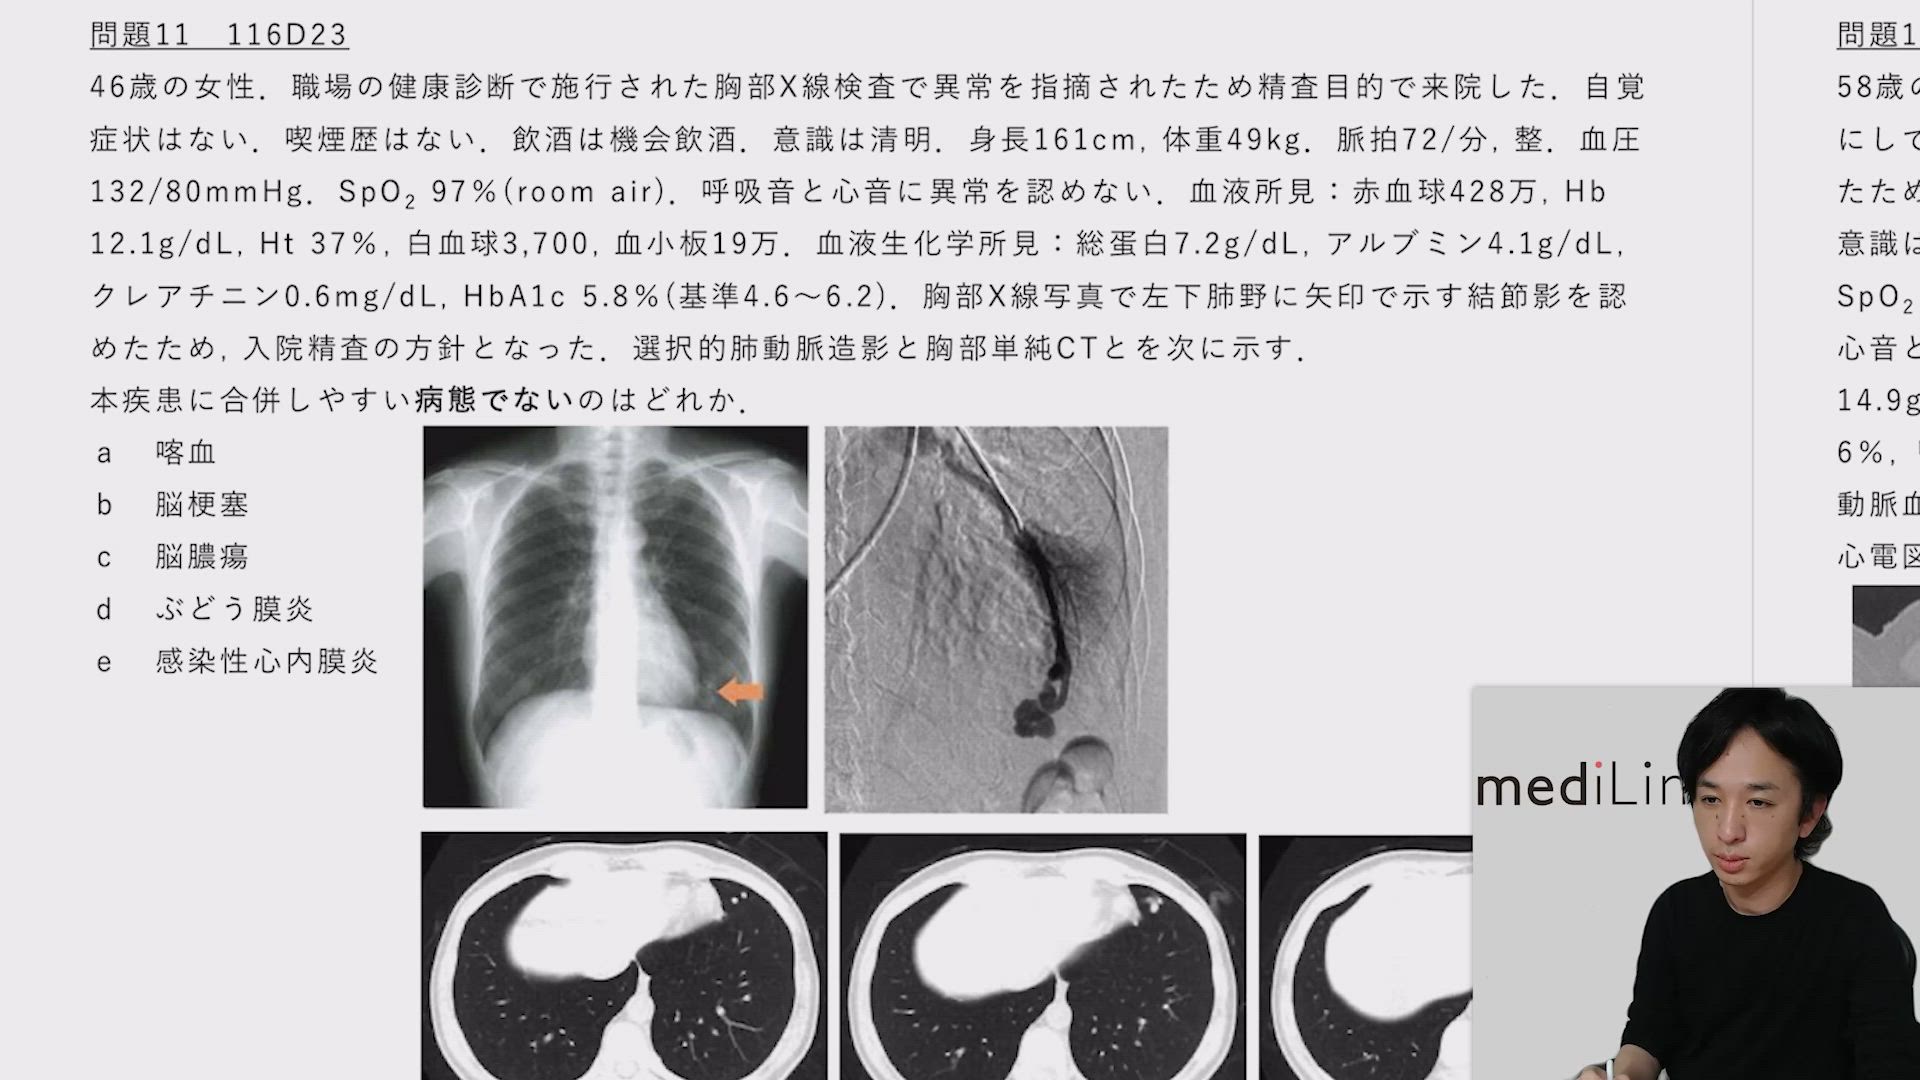

肺動静脈瘻